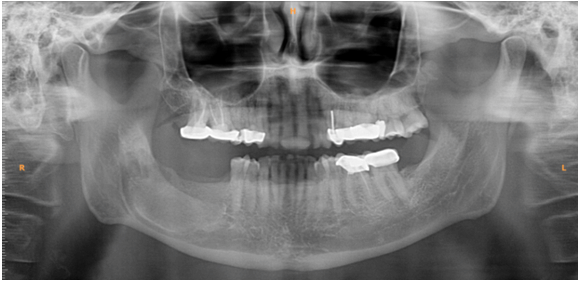

A 55-year-old male reported with pain in the lower right molar region since one month. Pain was insidious in onset, continuous, throbbing type and localized. Intraoral examination revealed missing 38, 48. On palpation, there was tenderness over right mandibular ramus region. Orthopantomogram revealed a well circumscribed unilocular radiolucency in the right mandibular body and angle region, extending from mesial aspect of 46 to 48 which is impacted (Figure 1). Root resorption of 46 and 47 was seen. Endodontically treated 14, 16, 17, 24, 25, 36 and impacted 48. Aspiration has shown serosanguineous fluid. Based on these clinical and radiographic findings a tentative diagnosis of unicystic ameloblastoma or Keratocystic odontogenic tumor was attained.

Figure 1: Preoperative orthopantomogram revealing the well circumscribed, unilocular radiolucency.